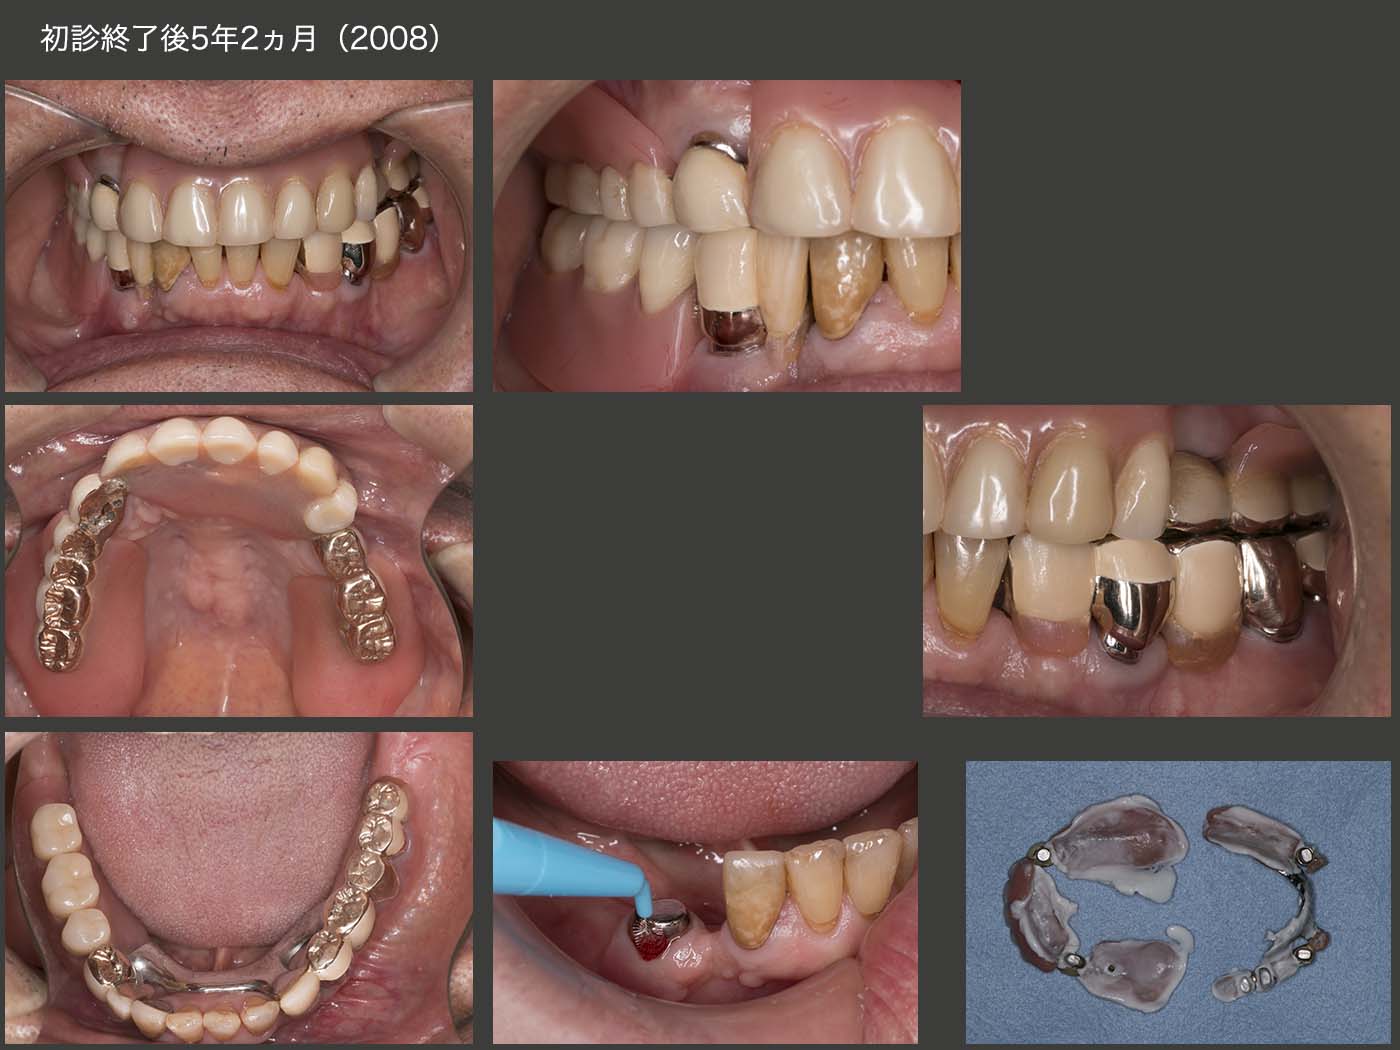

2015年6月,初診終了時の状態.初診より3年2ヵ月が経過してしまった.患者さんには長い間通院してくださり,心より感謝する次第である.上下顎とも支台歯が左右側にあることから,義歯の安定はすこぶるよい.左上のミニインプラントは役目が終わったので本来なら除去すべきところであるが,特に問題もないことからこのまま置いておくことにした.

義歯装着時の状態.通常ならばコーヌス義歯を選択することが多いが,この症例は左上5および右下4が移植歯であるため,流石にあまり側方力をかけたくないと思い,磁性アタッチメントを使用した.左下6の近遠心根は根面板を装着した.

根面アタッチメントを用いるとき,義歯で支台歯を覆ってしまうと,唾液による自浄作用が得られず,根面カリエスが生じやすい.そこで今回は,磁性アタッチメントおよび根面板の上に金属の上部構造体を製作し,支台歯の周囲をすべて開放した.

初診終了後5年2ヵ月,2020年8月の状態.右上6の口蓋根を移植した右下4の歯に,歯周ポケットが頰側で8mm認められた.実は18年7月のリコール時から右下4にフィステルが生じていた.その時歯周ポケットはなく,19年7月の時に6mm存在した.移植した際,根尖部をスーパーボンドで封鎖したが,不十分であったかもしれない.

義歯はまったく問題なく経過している.支台歯根面を開放したことは,根面マージン部の2次カリエス予防にとって,十分意義がある.